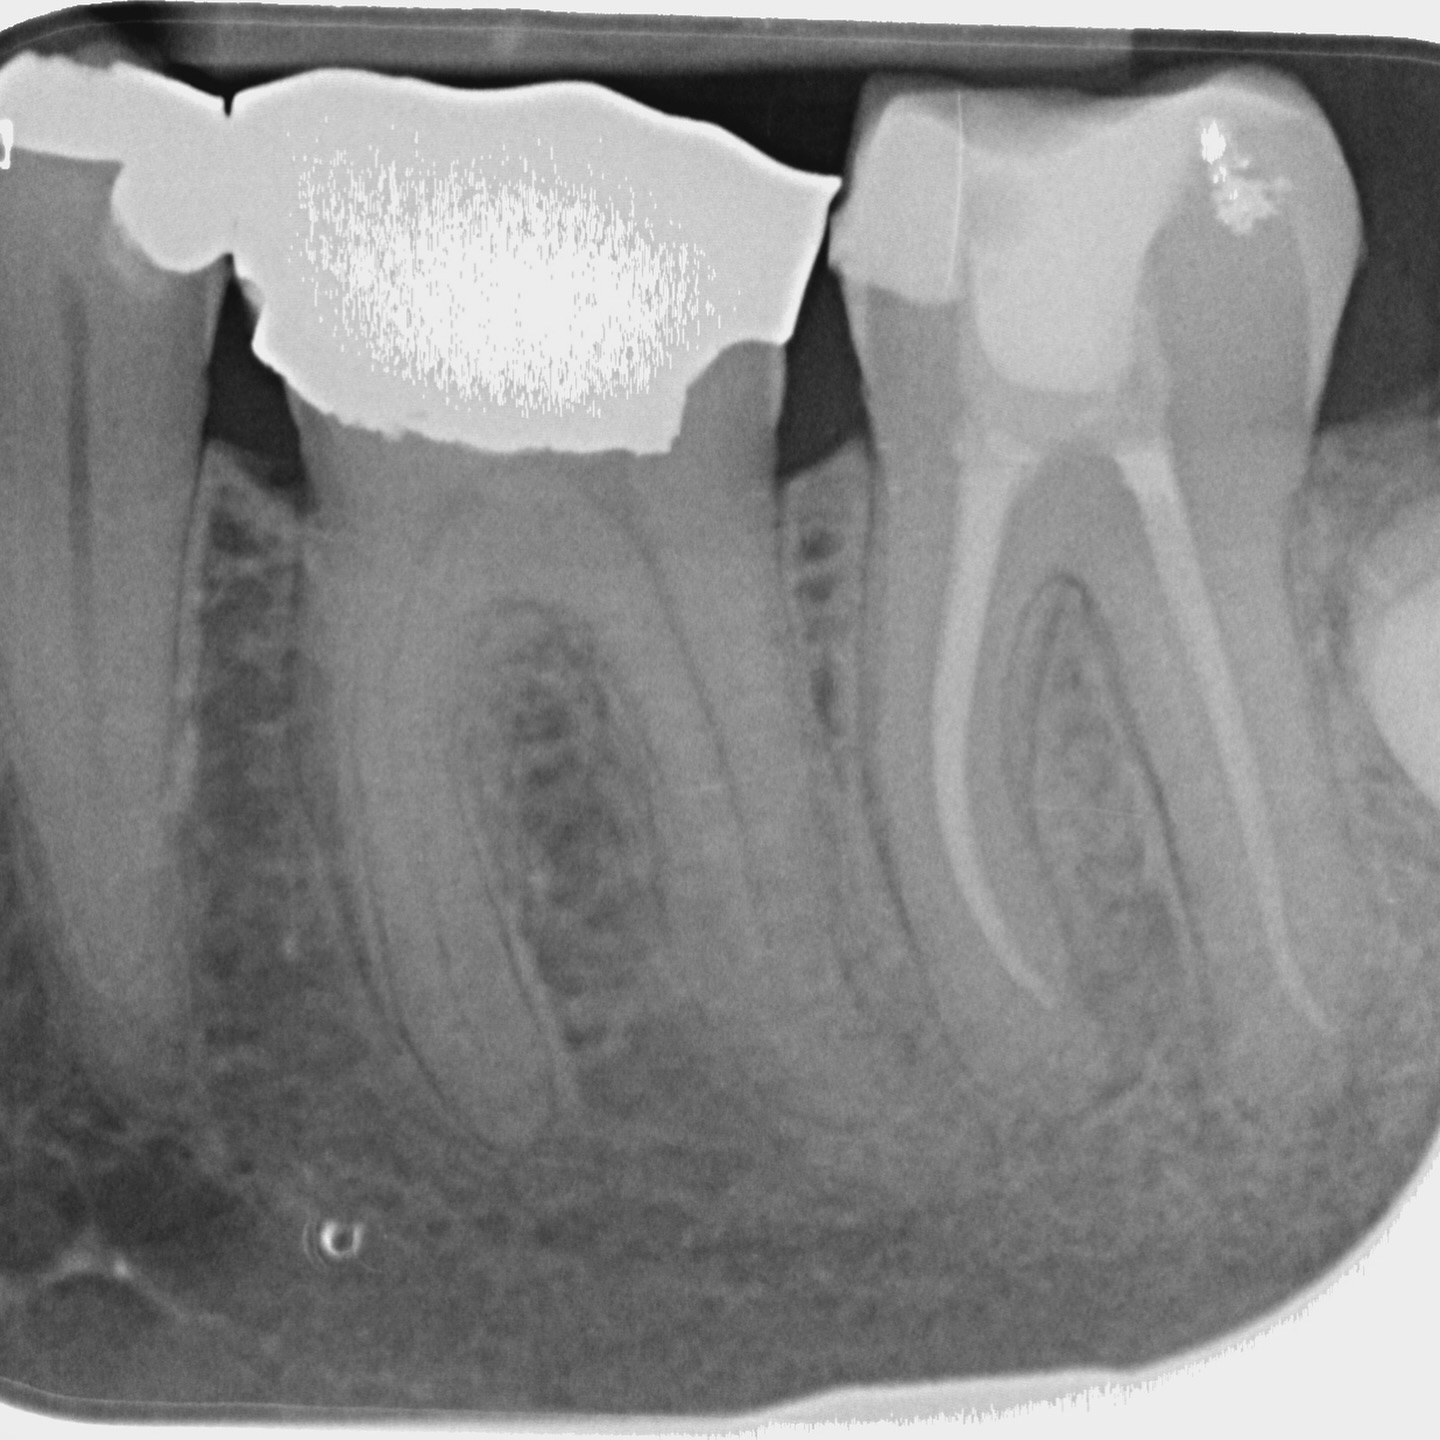

A comprehensive, non-specialist referral service for dental patients requiring affordable Endodontic treatment

Please email any relevant radiographs to rootreferral@gmail.com